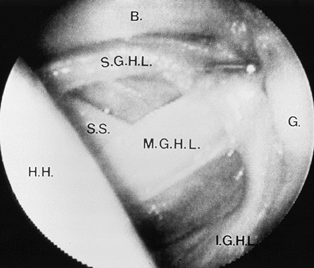

characterized by collagenous thickenings of varying development in its

anterior portion (Fig. 80.4) (11,13). These thick bands are called the glenohumeral ligaments due to their location along the glenoid rim. Table 80.1

![]() |

|

Figure 80.4. Arthroscopic view demonstrates normal anterior capsular ligamentous anatomy as viewed through a posterior arthroscopic portal (H.H., humeral head; G, glenoid; B, biceps tendon; S.G.H.L., superior glenohumeral ligament; S.S., subscapularis; M.G.H.L., middle glenohumeral ligament; I.G.H.L.,

inferior glenohumeral ligament). (From Turkel SJ, Panio MW, Marshall JL, Girgis FG. Stabilizing Mechanisms Preventing Anterior Dislocation of the Glenohumeral Joint. J Bone Joint Surg [Am] 1981;63:1209, with permission.) |